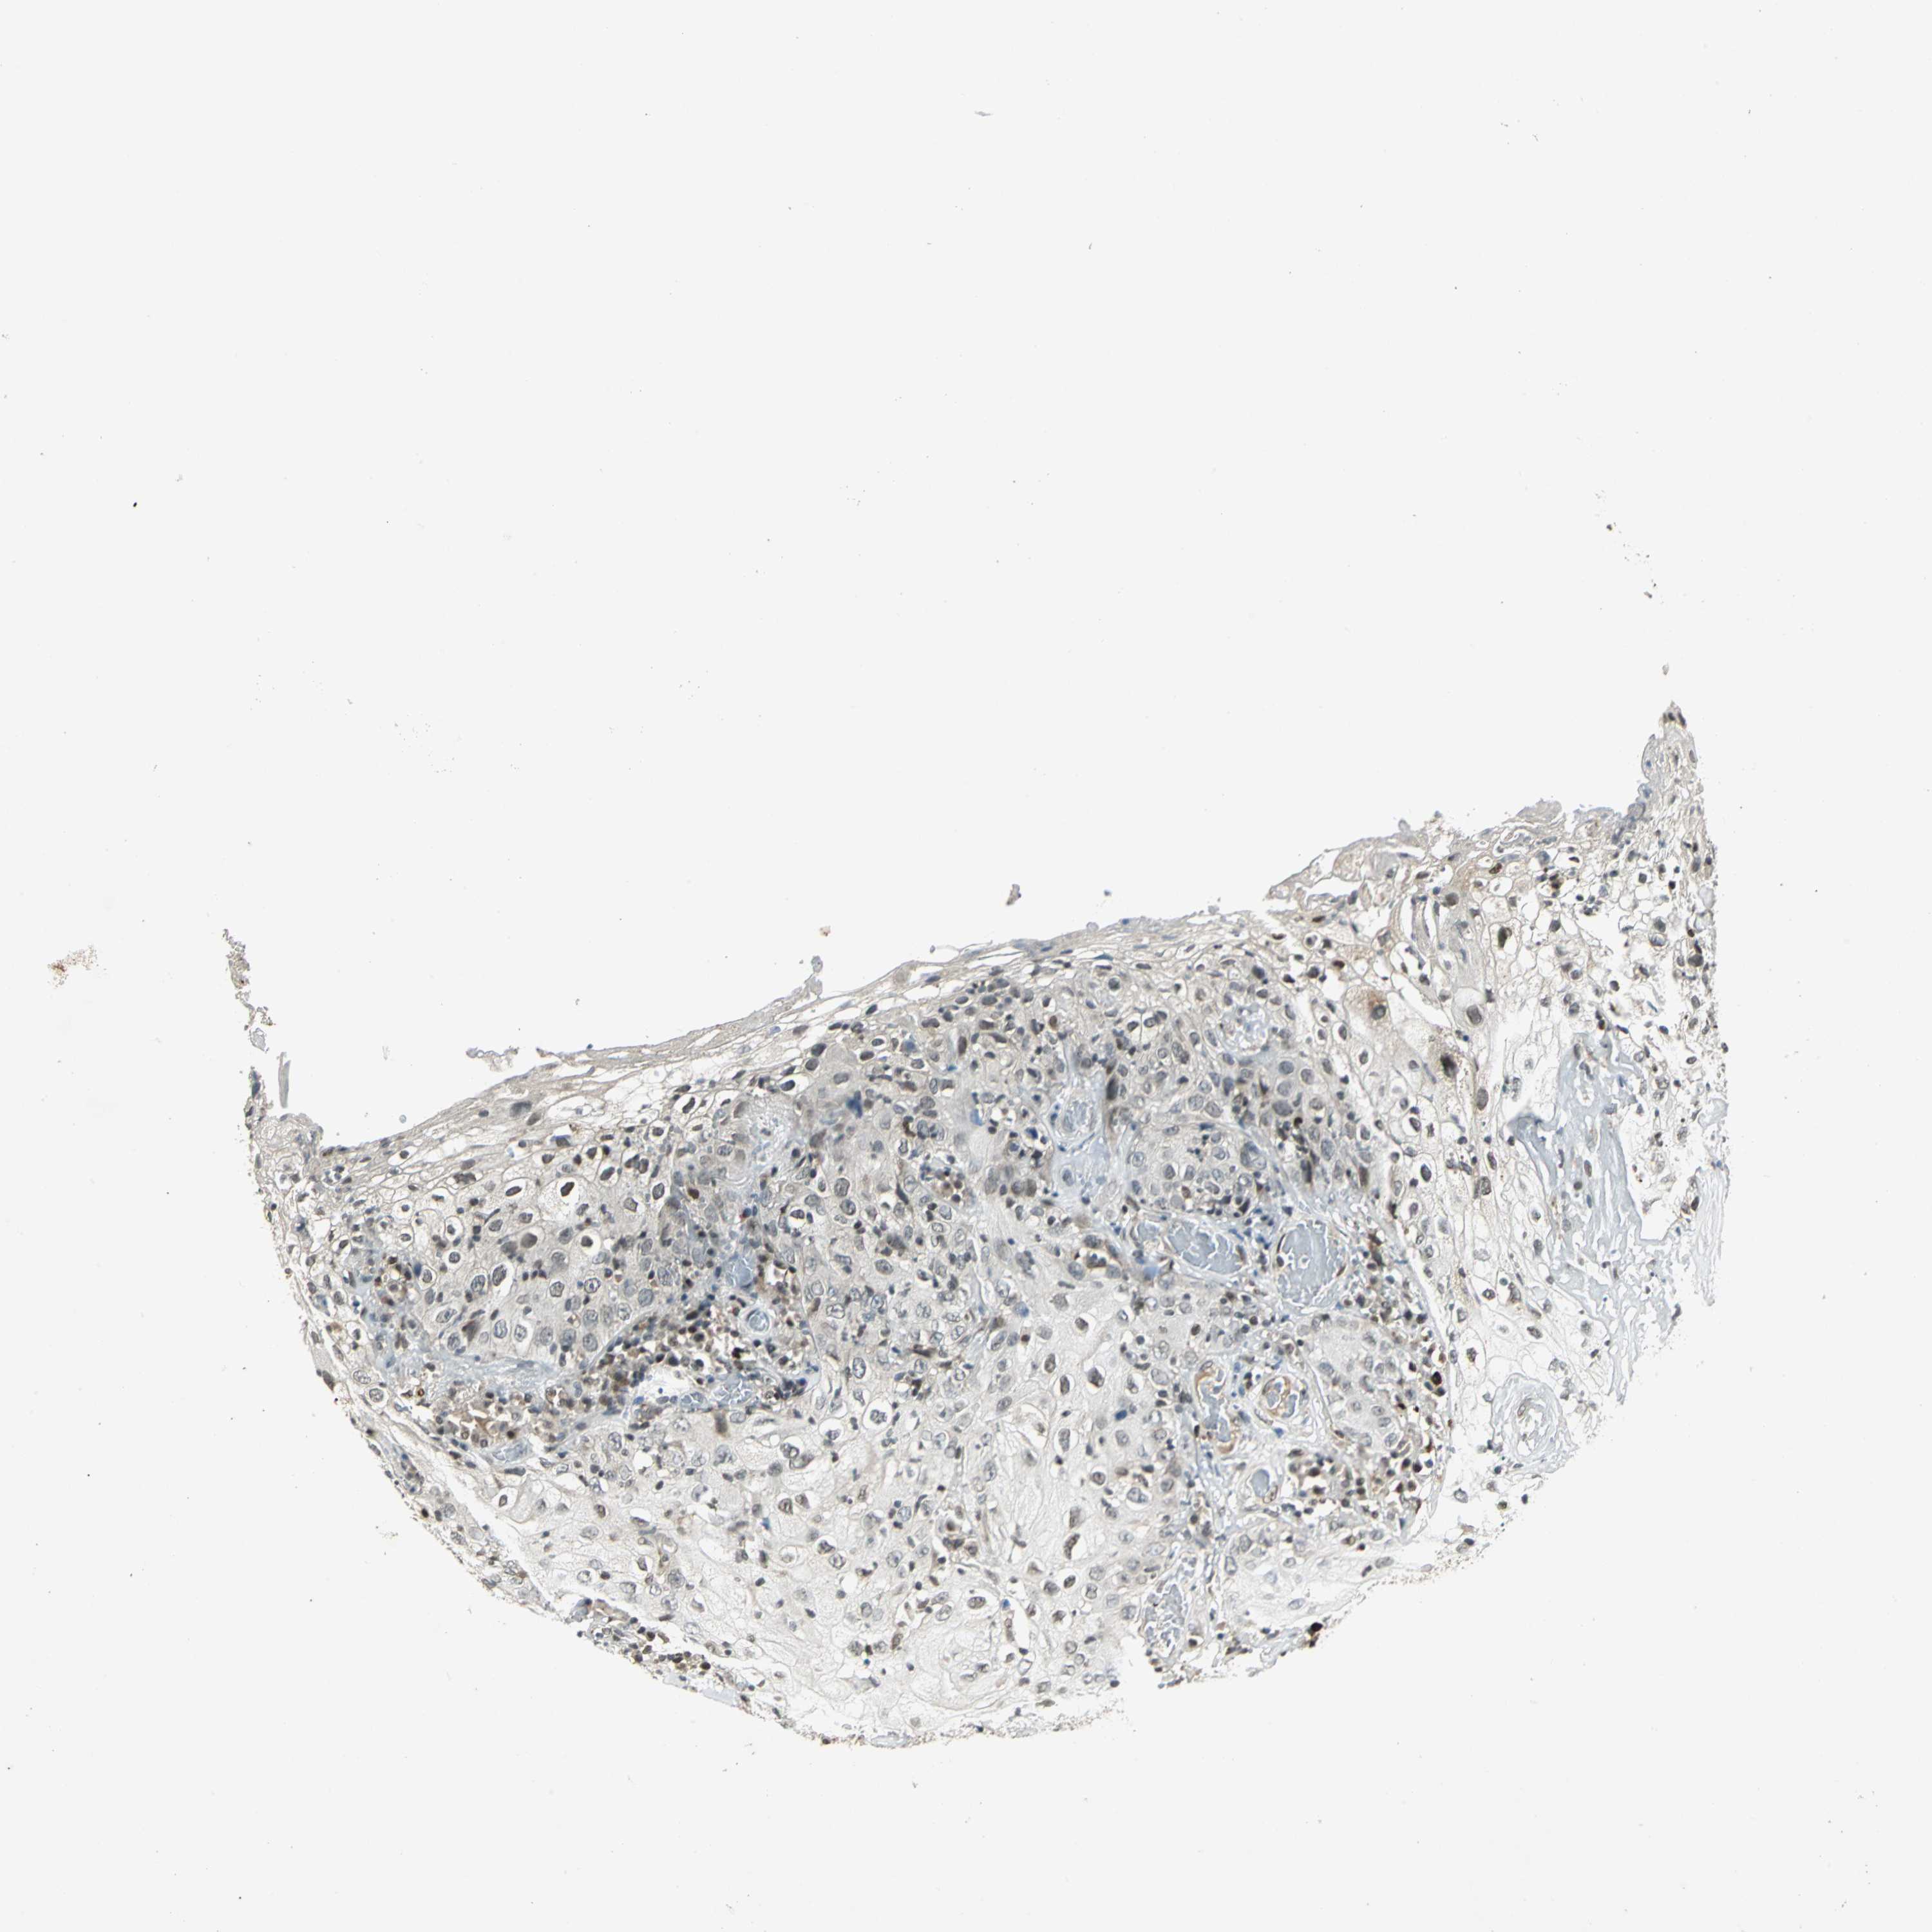

Basal cell and squamous cell cancer

SKIN CANCER - Protein expressioni

A mouse-over function shows sample information and annotation data. Click on an image to view it in a full screen mode. Samples can be filtered based on level of antibody staining by selecting one or several of the following categories: high, medium, low and not detected. The assay and annotation is described here.

Antibody stainingi

Antibody staining in the annotated cell types in the current human tissue is reported as not detected, low, medium, or high, based on conventional immunohistochemistry profiling in selected tissues. This score is based on the combination of the staining intensity and fraction of stained cells.

Each image is clickable and will lead to virtual microscopy that enables deeper exploration of all samples and also displays staining intensity scores, fraction scores and subcellular localization as well as patient and tissue information for each sample.

Antibody CAB004551

Staining

Medium

Intensity

Moderate

Quantity

75%-25%

Location

Nuclear

Cytoplasmic/membranous

Basal cell carcinoma